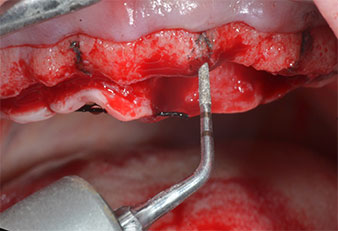

Abb. 2: Nach dem Kieferkammschnitt und der Präparation der Mukoperiostlappen werden die Implantatpositionen auf den Knochen übertragen.

Ein flammenförmiges, diamantiertes piezochirurgisches Instrument (Piezomed I1) wurde verwendet, um die Implantatpositionen zu markieren und die Pilotpräparationen durchzuführen (Abb. 3). Dabei wurde darauf geachtet, eine Auf- und Abbewegung mit reduzierter Leistung, voller Spülung und niedrigem Druck (unter 300 g) anzuwenden. Als Nächstes wurde ein Pilotinstrument (Piezomed I2A/I2P) zur initialen Erweiterung der Implantatlager auf einen Durchmesser von 2 mm verwendet (Abb. 4), gefolgt von einem 3-mm-Instrument (Abb. 5).

Ultraschallmarkerinstrument Piezomed

Abb. 3: Die Präparation mit dem Ultraschallmarkerinstrument Piezomed I1 erfolgt mit einer Auf- und Abbewegung, parallel zur Längsachse des Arbeitsteils.